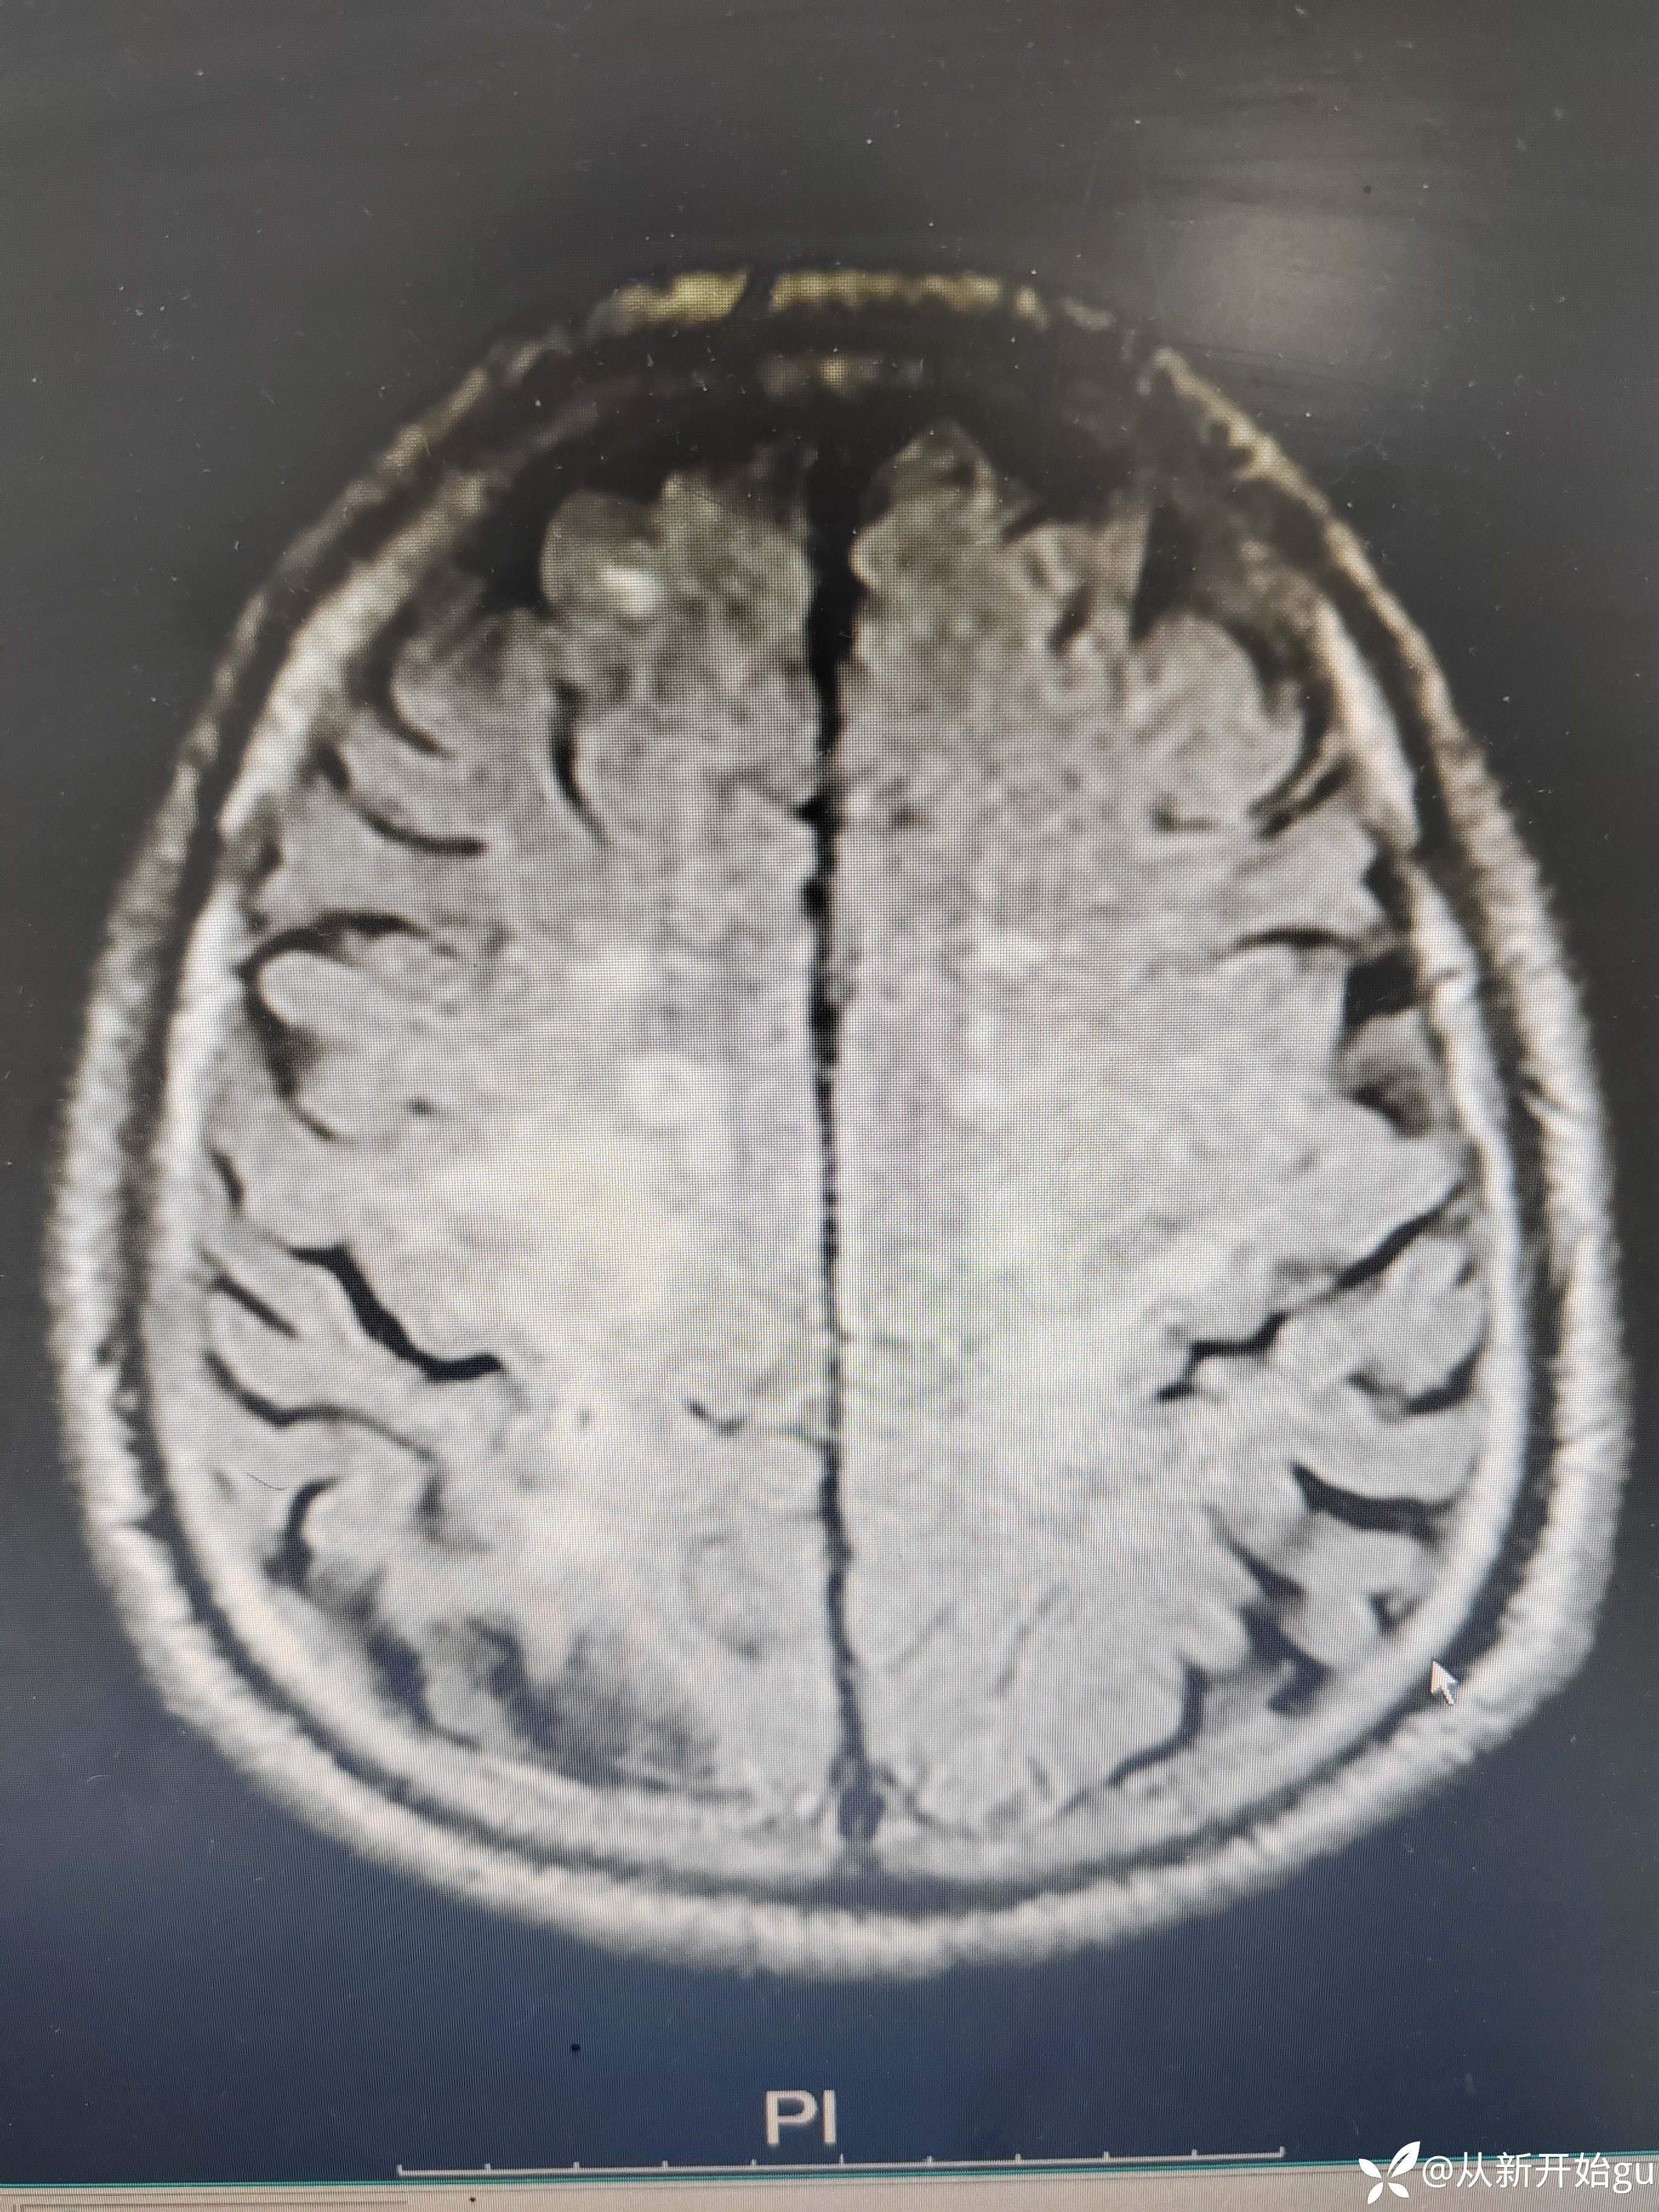

患者男性53岁,主因被发现左下肢活动障碍2.5小时来院,(患者下夜班,于上午9点休息,下午3点醒后出现症状)。既往脑梗死病史9个月,遗留言语不利及口角歪斜的症状。查体:右侧鼻唇沟稍浅,神舌右偏,左侧下肢肌力4级,左侧指鼻试验欠稳准,左侧巴氏征阳性。外院完善颅脑CT无出血改变。来院后完善核磁检查如图所示。

考虑诸多因素在里面,未与溶栓。